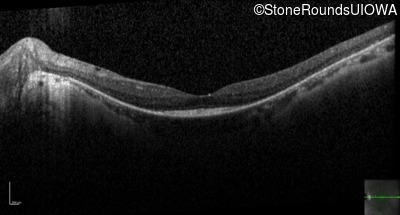

Optical Coherence Tomography - Right - 20/30 +2

Exemplar / OCT Stack

OCT Stack